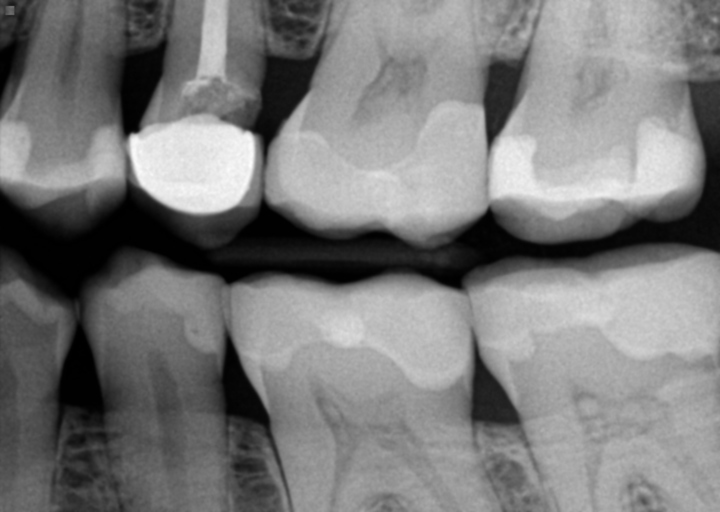

My root canal crown has fell off again after a little over a month . Now it is hurting why is that?

Hi . My crown fell off my root canal . I had the root canal done a little over a month ago . A week later the crown fell off . I went back and they put a new crown on . But now it fell off . The root canal tooth also seems to hurt in a way . Its red...